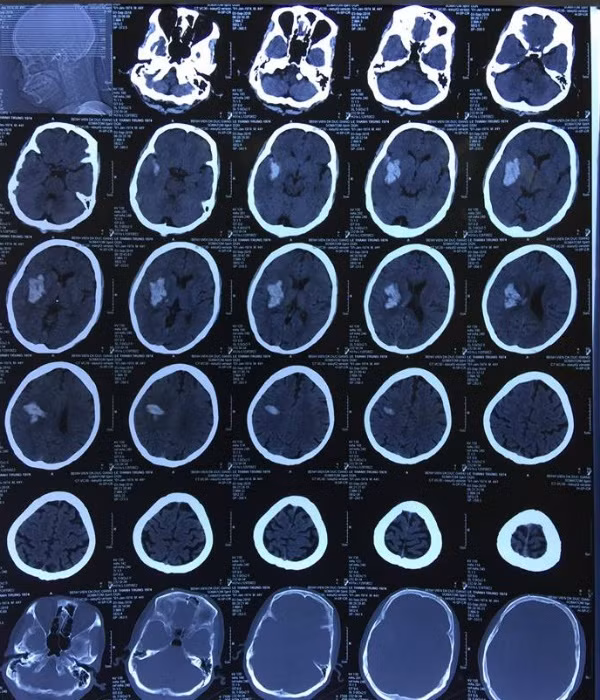

Ngày 3/9, anh Lê T.T (44 tuổi, Gia Lâm, Hà Nội) nhập viện trong tình trạng đau đầu, nói ngọng. Các kết quả chụp CT sọ não cho thấy anh T. có khối máu tụ trong não, cần phải theo dõi sát sao.

Ngay lập tức, các bác sĩ đã chụp lại CT sọ não, kết quả cho thấy khối máu tụ trong não đã lan rộng, kích thước to gấp 3 – 4 lần gây chèn ép các tổ chức xung quanh.

Hình ảnh chụp CT của bệnh nhân xuất huyết não được cứu sống.